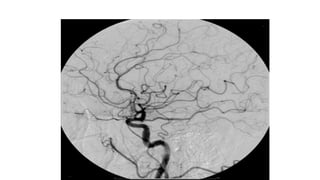

• Digital subtraction angiography (DSA) is a new radiographic

technology used in diagnosing vascular disease

• The digitalized image information makes it possible to “subtract” the

pre contrast images from those obtained after contrast injection so as

to visualize arterial structures without direct arterial puncture and

injection

• DSA is a gold standard investigation for renal artery stenosis, cerebral

aneurysms & arteriovenous malformations (AVM).

DSA

• Image contrast can be enhanced electronically and image contrast is

improved by subtraction techniques which provide instantaneous

viewing of the subtracted image during passage of a bolus of contrast

medium.

• So Digital fluoroscopy provides better contrast resolution through

post processing of image subtraction.